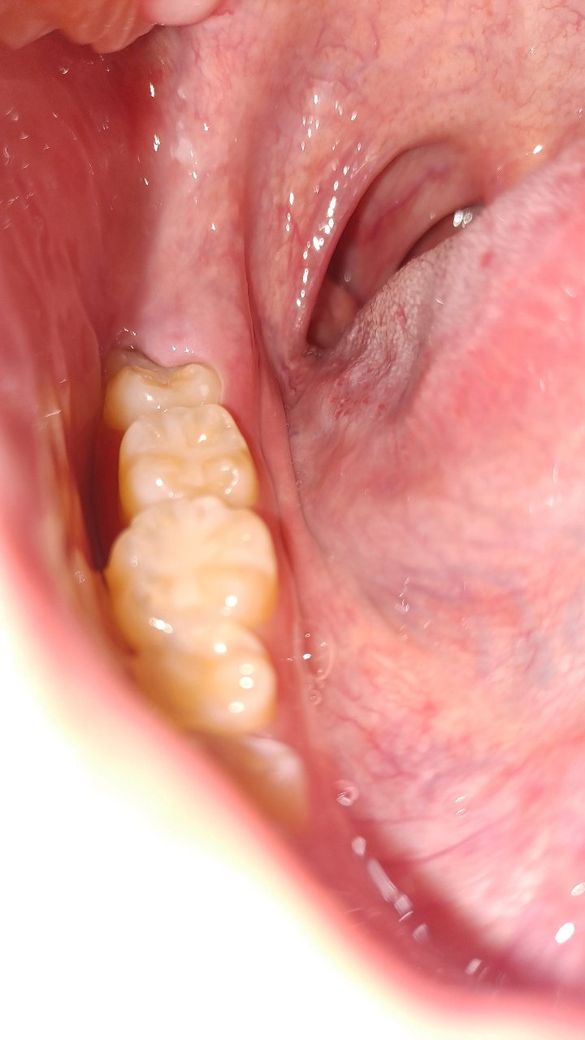

사진에 보이는 아래 사랑니는 잇몸안에 이물질이 잘 저류될수 있는 형태이기 때문에 잇몸을 다듬거나 발치를 해주는것이 좋을수도 있습니다.

아래쪽은 부분 매복되어 있어 음식물이 자주 저류되어 염증 및 충치 등의 위험이 커 보입니다. 현재 통증으로 보아서는 시간이 지나면 사라져 다시 불편감이 없어질 수 있어 보이나 시간이 지남에 따라 이러한 증상이 반복된다면 추후에 잇몸뼈가 녹을 수도 있습니다.

아래치아는 부분매복이 되어있습니다. 이런경우 반복적으로 통증이 생길 수 있습니다.

치관주위염이 의심되는 상황입니다. 사랑니 주변의 잇몸이 사랑니를 덮어 그 사이 공간에 음식물이 끼게되고 청소가 잘되지 않아 내부에서 부패가 일어나게되면 만성적으로 염증이 반복됩니다.

사랑니가 비교적 바르게 난 경우로 보이나, 잇몸 밖으로 완전히 맹출하지 못한 경우로 보입니다.

이런 경우에는 말씀하신 것처럼 사랑니와 잇몸 사이에 음식물이 끼기 쉽고, 이를 빼내는 것이 쉽지 않아 구강위생관리가 어렵습니다.

해당 부위에 음식물이 저류하게 되면서 염증이 발생하고, 반복적으로 붓고 피가 나며 통증이 발생할 수 있습니다.

사랑니 뒤쪽 잇몸사이가 부어있는걸로 보입니다.

사랑니 근처에 음식물잔사가 남아있어 잘 제거되지 않을때 이런식으로 붓기, 통증이 나타날 수 있습니다.